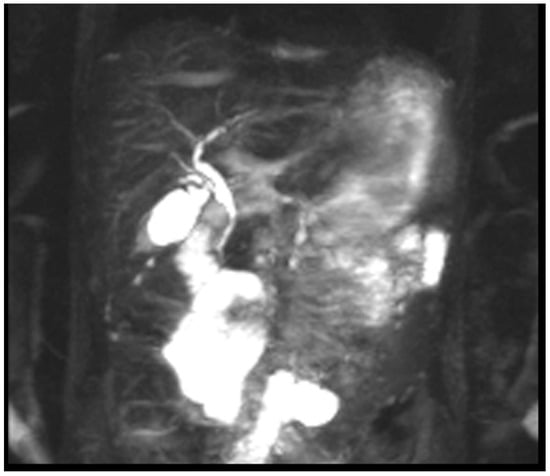

- An MRI with magnetic resonance cholangiopancreatography (MRCP) showed slight beading of the common bile duct, common hepatic duct, and proximal hepatic duct; the common bile duct was dilated to 10 mm in width (see Figure 2).